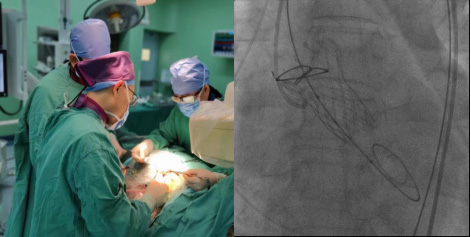

经导管主动脉瓣植入术(TAVI)

经股动脉或心尖路径植入主动脉瓣膜,适用于高危、重度主动脉瓣狭窄或关闭不全患者。手术在杂交手术室完成,无需体外循环,降低手术风险,提高生活质量。对合并冠心病的患者,可同期处理冠脉病变。